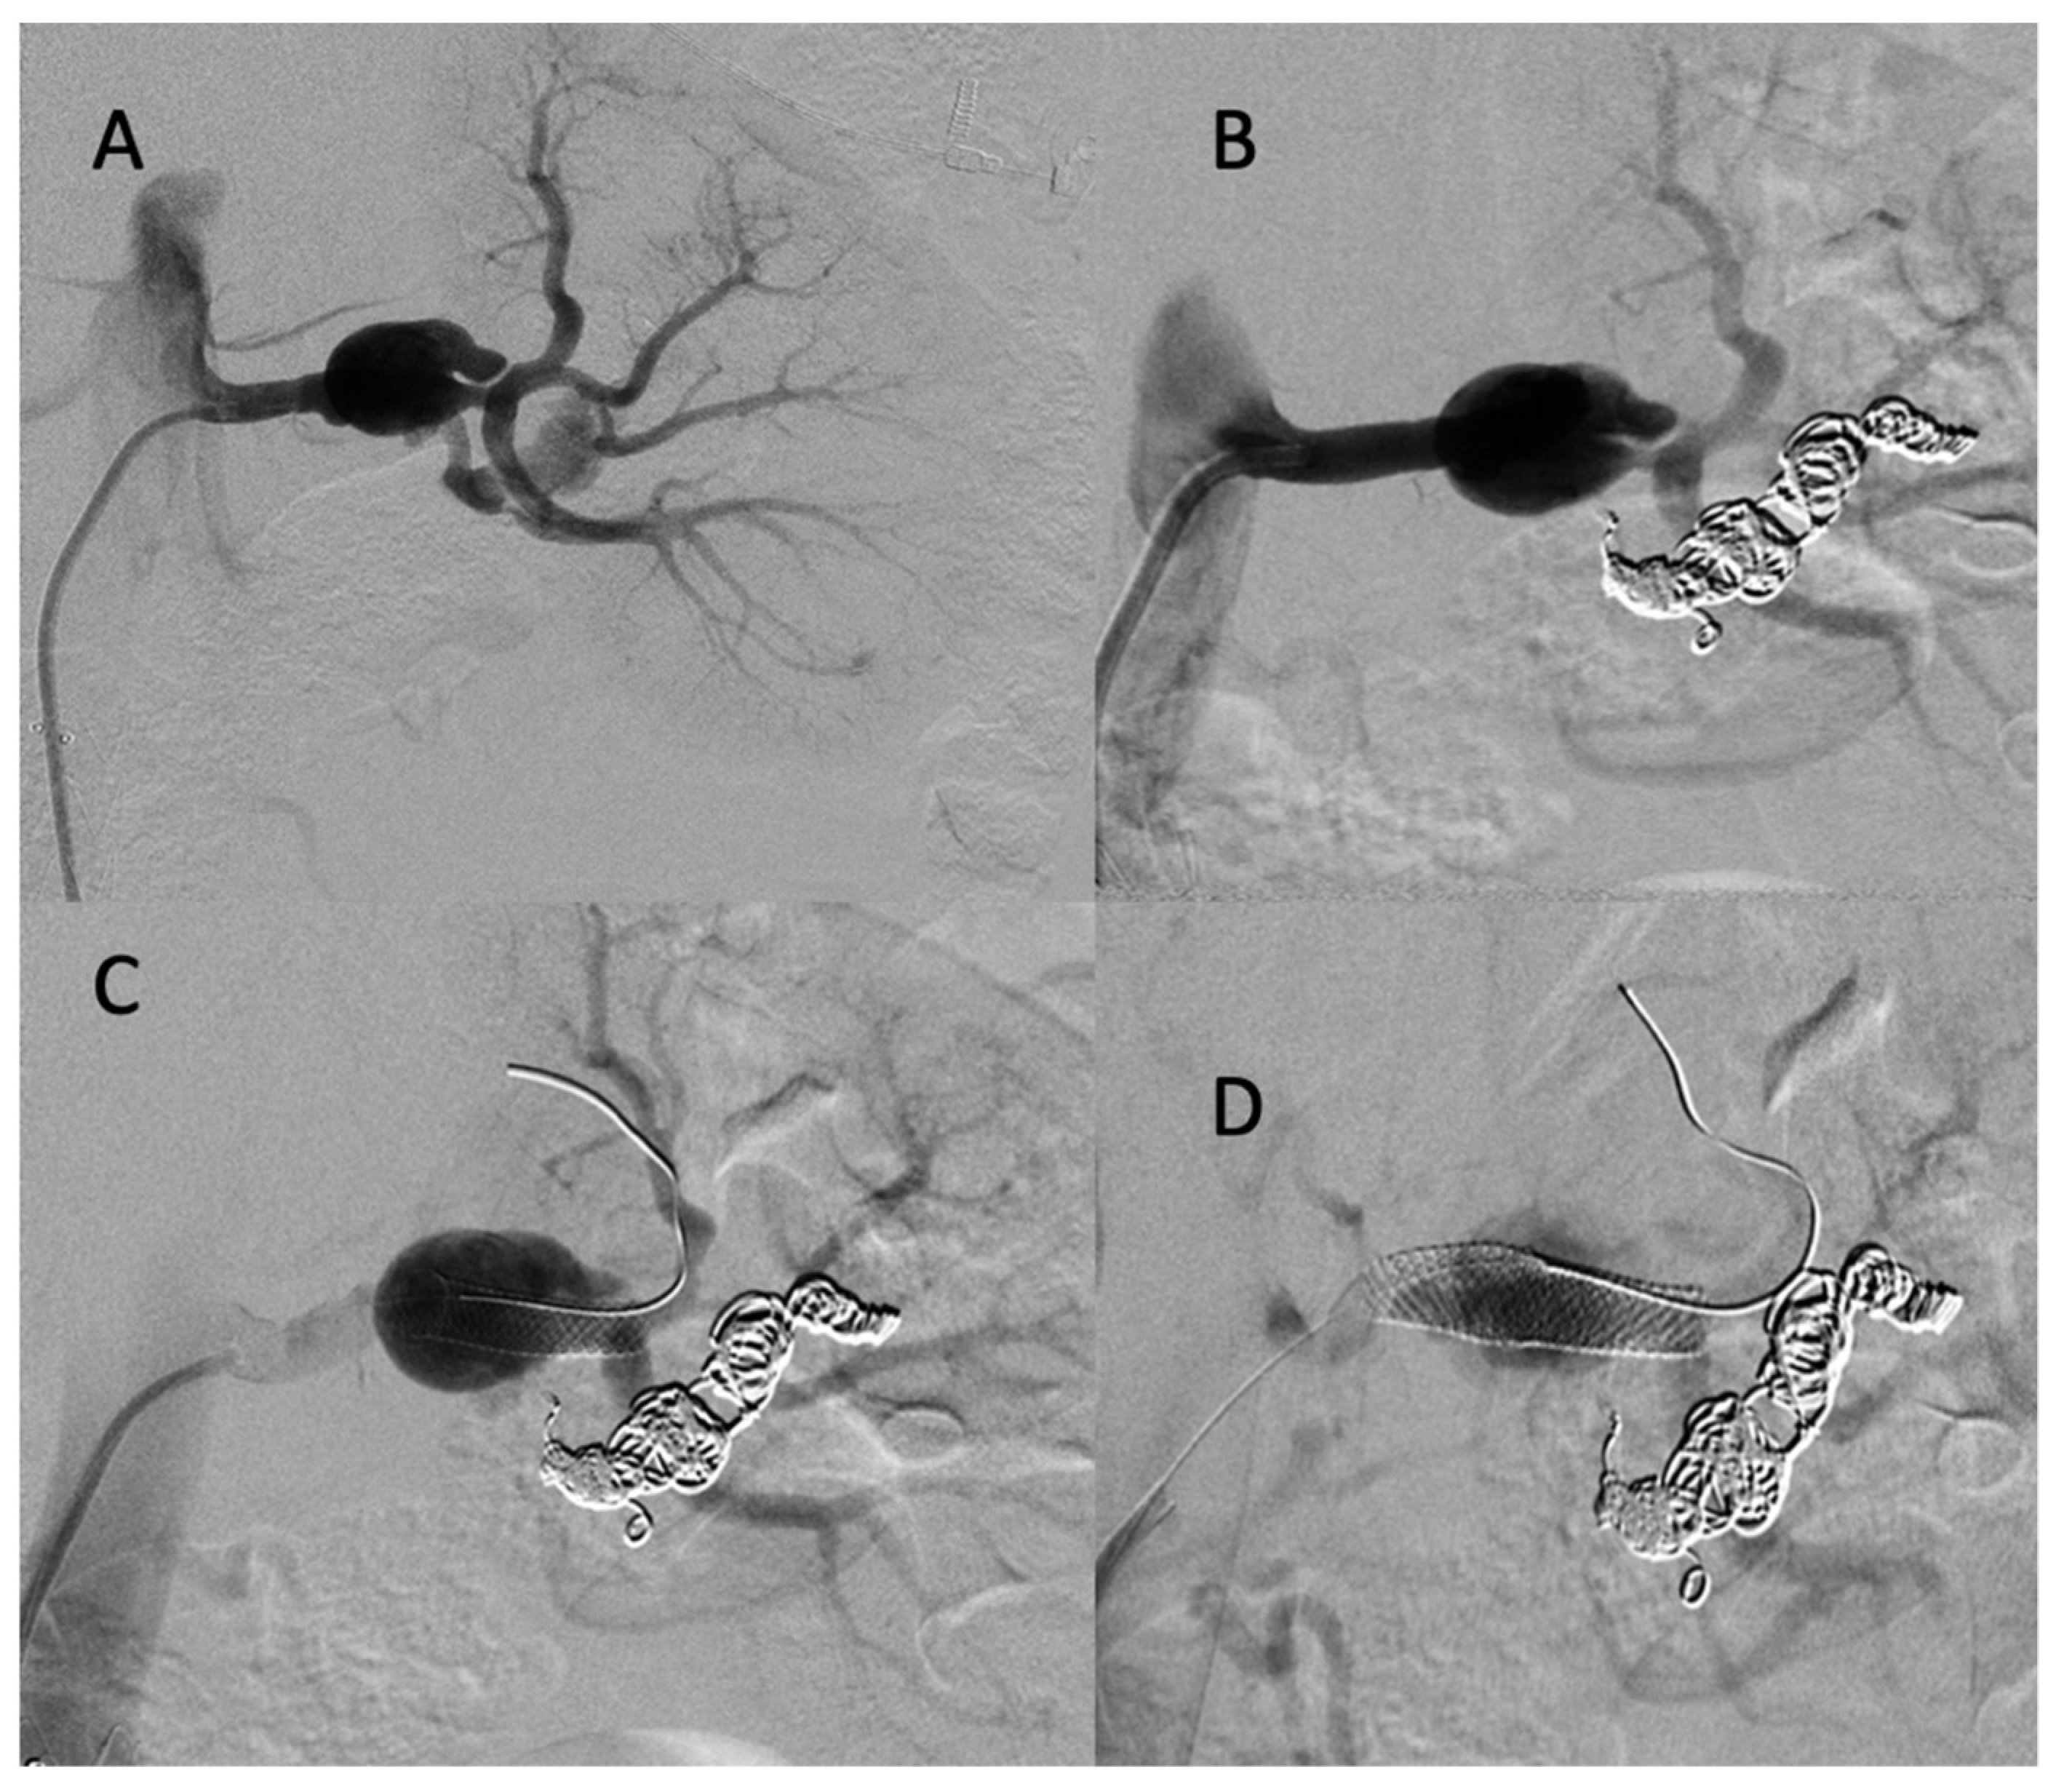

A 25-year-old male patient, with a familial history aortic rupture leading to the sudden death of his father in 1999, was referred to our hospital after the appearance of a left groin hematoma. An enhanced abdominal and pelvic CT scan revealed an aneurysm of the splenic artery measuring 30 × 25 mm and a recent dissection of the left common iliac artery, with a maximum iliac diameter of 12 mm (Figure 3A,B). In his medical history, he complained of abdominal pain within the left hypochondrium for the past 8 months following physical exercise. After a multidisciplinary evaluation, we first decided to embolize the splenic aneurysm using coils to prevent the risk of rupture. Under general anesthesia, a 6 F introducer was inserted into the left humeral artery using the Seldinger technique. Two-dimensional/three-dimensional fusion with preoperative CT angiography was performed to guide the catheter and microcatheter for the more rapid catheterization of the aneurysm and to decrease the radiation exposure (Figure 3C). We catheterized the celiac trunk artery using a 6 F ENVOY catheter (Codman-USA) and then catheterized the aneurysm using a Progreat 2.8 F microcatheter (Terumo-Tokyo, Japan). We started to exclude the outflow of the aneurysm with several Ruby coils (Penumbra-Alameda, CA, USA). We then filled the aneurysm with multiple coils starting with a 3D Ruby standard coil of 34 mm diameter and after decreasing the diameter of the coils using interlock detachable coils (IDCs, Boston Scientific, Marlborough, MA, USA), Nester coils (COOK 6 USA), and packing coils (Penumbra-Alameda, CA, USA), and we occluded the aneurysm inflow using Ruby standard coils (Penumbra-Alameda, CA, USA) (Figure 3D).

Figure 3.

(A,B) Abdominal CT angiogram with 3D image and arteriography with image fusion (C,D) showing the aneurysm in the splenic artery (arrows). We marked the proximal and distal extremities of the neck of the aneurysm (head arrow), and then we started the embolization using multiple coils after, within, and before the aneurysm.

Successive CT scan follow-up revealed rapid aneurysmal growth of his left common iliac artery with a 12 mm increase in diameter within one week. The patient complained of left groin pain. A hybrid surgical treatment of left iliofemoral bypass and endovascular exclusion of the internal iliac artery was selected (Figure 4).

Figure 4.

(A) Abdominal CT angiogram with 3D image showing the dissection of the left common iliac artery (arrow); (B) arteriography shows the left iliofemoral bypass (star) and dissection of the left common iliac artery (arrow); (C) occlusion of the left internal and external iliac arteries by coils and then a plug (head arrow); (D) arteriography final shows the permeability of left iliofemoral bypass (star).

During the iliofemoral bypass, a 6 Fr introducer was inserted into the left femoral artery. The left internal iliac artery was catheterized using both a 4 F cobra catheter (COOK-MEDICAL) and a Progreat 2.7 F catheter (Terumo-Tokyo, Japan). The internal iliac artery trunk was occluded using 6 × 60 POD coils (Penumbra-Alameda, CA, USA). Then, the common internal iliac artery was occluded using second-generation 10 mm Amplatzer vascular plugs and several coils (ABBOTT). The external iliac artery was occluded by several Amplatzer Plugs (ABBOTT). One week after the intervention, he complained of acute epigastric pain and presented with hemorrhagic shock. An enhanced abdominal and pelvic CT scan showed hemoperitoneum with aneurismal rupture of the left hepatic artery and an aneurysm of the celiac trunk and common hepatic artery (Figure 5). The patient was referred in extreme emergency to the interventional radiologist. A 6 F femoral access was performed to access the celiac trunk using the 6 F RDC catheter (Cordis-Santa Clara, CA, USA). Then, the left hepatic artery aneurysm was catheterized using a Progreat 2.7 F microcatheter (Terumo-Tokyo, Japan). The rupture of the left hepatic artery was confirmed on digital subtraction angiography (DSA), and the vessel was occluded using cyanoacrylate glue and multiple coils. DSA of the celiac trunk revealed an aneurismal evolution of the celiac trunk and the common hepatic artery with an occlusion of the common hepatic artery before the gastroduodenal artery. The common hepatic artery and celiac trunk were occluded using ethylene vinyl alcohol copolymer (Onyx, ev3, USA), several interlocking coils, and IDS (Boston Scientific, Marlborough, MA, USA) (Figure 5) without any complications during the procedure.